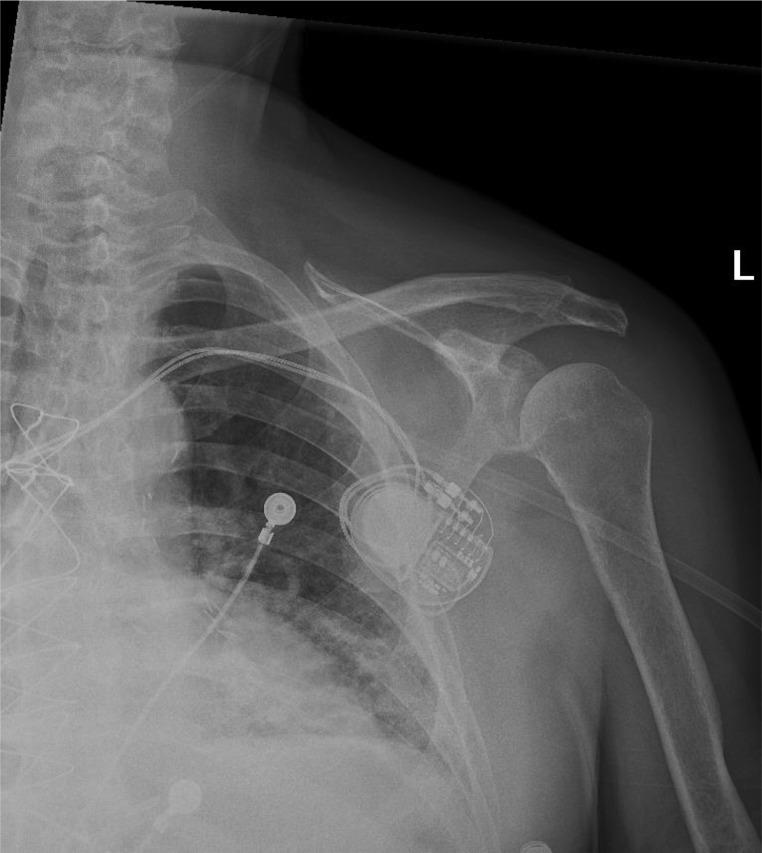

Hemarthrosis secondary to heparin use is a scarce event, especially in patients with no underlying thrombophilia or platelet disorders. Although previously associated with thrombophilia, platelet disorders, or secondary to fibrinolytic therapy, to date, there are very few reported cases in contemporary literature for heparin-induced hemarthrosis. In this article, we report a case of left shoulder joint inferior subluxation secondary to heparin-induced hemarthrosis in an 81-year-old male with an extensive cardiac history and multiple comorbidities. This case report depicts a rare event and discusses its clinical implications aiding healthcare professionals in an early diagnosis and timely management.

肝素使用继发的关节积血是一种罕见事件,尤其在没有潜在血栓形成倾向或血小板疾病的患者中。尽管以前与血栓形成倾向、血小板疾病相关,或继发于纤维蛋白溶解疗法,但迄今为止,当代文献中关于肝素诱导的关节积血的报道病例非常少。在本文中,我们报告了一例81岁男性因肝素诱导的关节积血继发左肩关节半脱位的病例,该患者有广泛的心脏病史和多种合并症。本病例报告描述了一个罕见事件,并讨论了其临床意义,以帮助医护人员进行早期诊断和及时处理。